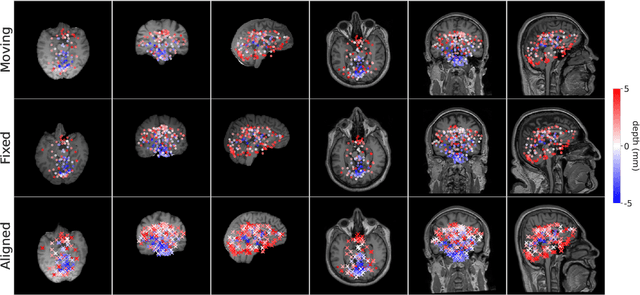

Abstract:We present a keypoint-based foundation model for general purpose brain MRI registration, based on the recently-proposed KeyMorph framework. Our model, called BrainMorph, serves as a tool that supports multi-modal, pairwise, and scalable groupwise registration. BrainMorph is trained on a massive dataset of over 100,000 3D volumes, skull-stripped and non-skull-stripped, from nearly 16,000 unique healthy and diseased subjects. BrainMorph is robust to large misalignments, interpretable via interrogating automatically-extracted keypoints, and enables rapid and controllable generation of many plausible transformations with different alignment types and different degrees of nonlinearity at test-time. We demonstrate the superiority of BrainMorph in solving 3D rigid, affine, and nonlinear registration on a variety of multi-modal brain MRI scans of healthy and diseased subjects, in both the pairwise and groupwise setting. In particular, we show registration accuracy and speeds that surpass current state-of-the-art methods, especially in the context of large initial misalignments and large group settings. All code and models are available at https://github.com/alanqrwang/brainmorph.